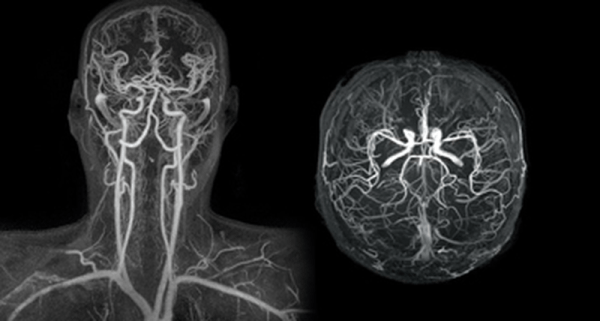

Ένα σύγχρονο και τεχνολογικό ιατρείο αγγειοχειρουργού θα ενσωματίζει πολλές σύγχρονες τεχνολογίες και πρακτικές προκειμένου να παρέχει υψηλής ποιότητας φροντίδα για προβλήματα που σχετίζονται με τον αγγειακό σύστημα. Ορισμένα χαρακτηριστικά που μπορεί να έχει ένα τέτοιο ιατρείο περιλαμβάνουν: